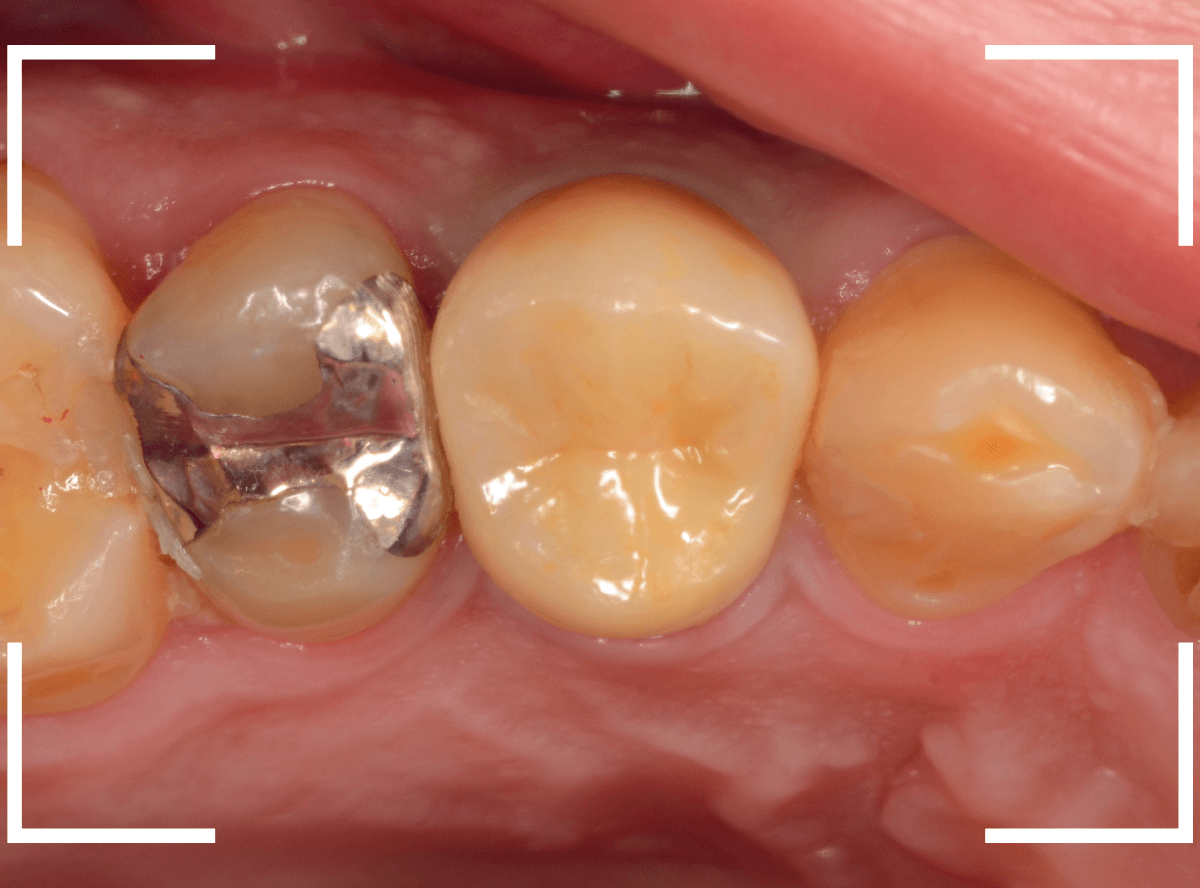

頃合いをみて、歯の型をとってさし歯の製作に移ります。

今回は、オール・ジルコニア・クラウンで製作することになりました。

最終setした状態です。

今回は厳しい条件でしたが、なんとか最終setまでする事ができました。

| 治療回数 | 5回 |

| 治療期間 | 6週間 |

| 費用 | オール・ジルコニア・クラウン (100,000円) +保険治療費用 |

(2024年12月)